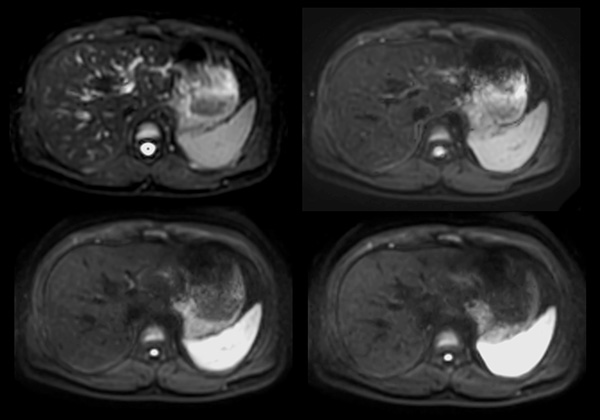

Axial mDIXON (W, IP, OP, F)